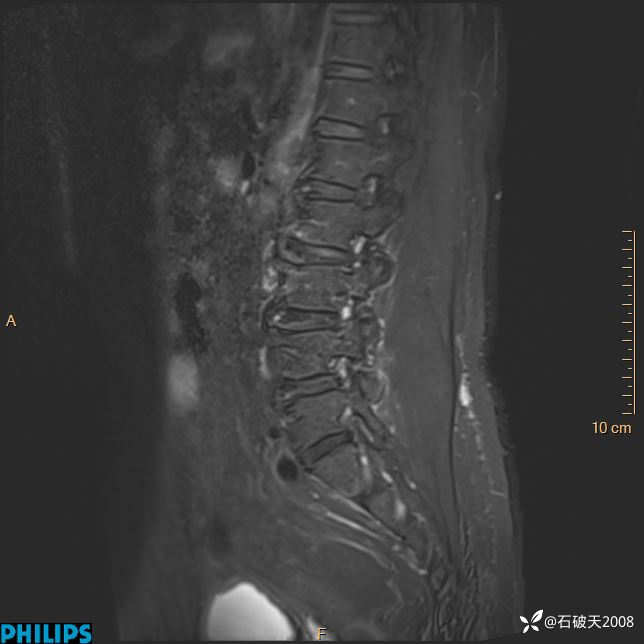

2023年3月份MRI影像

T2矢状位压脂